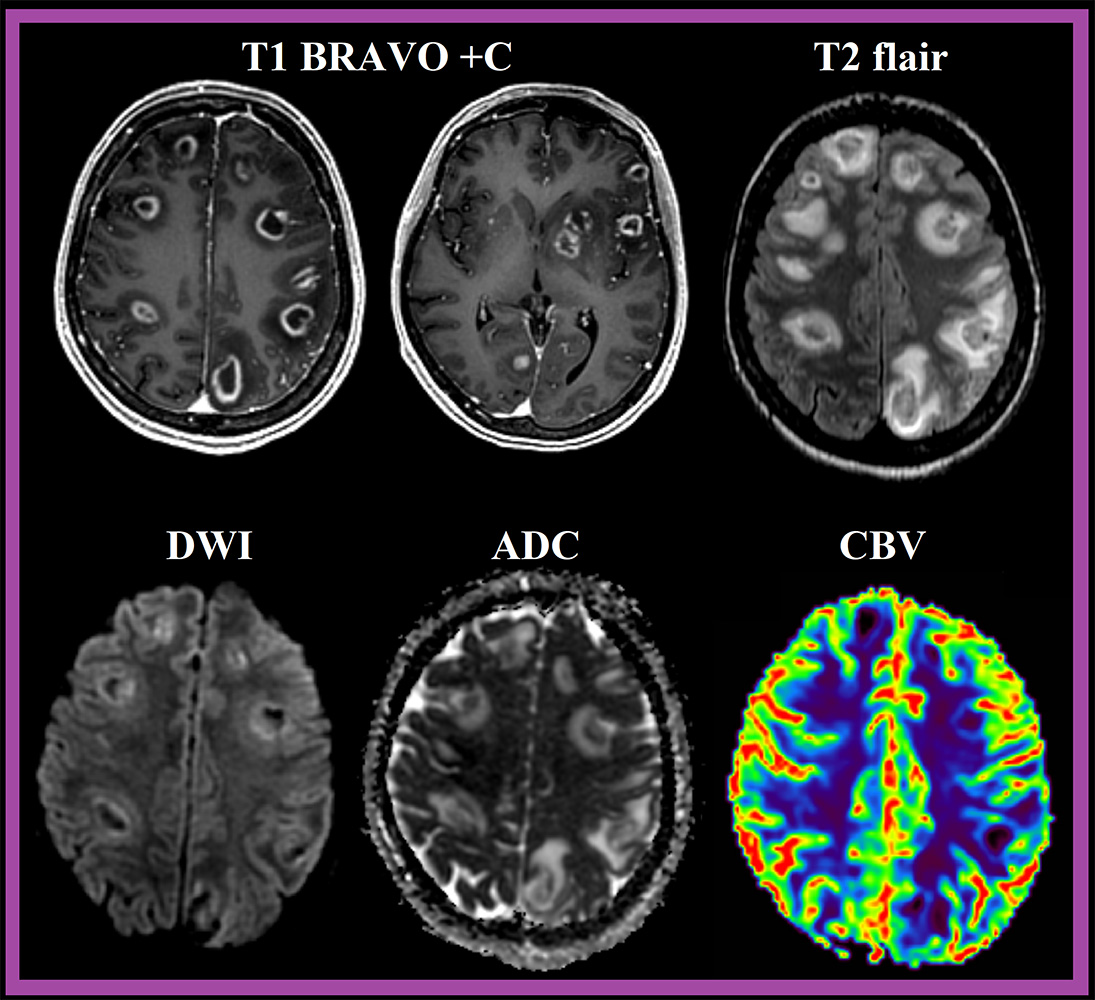

При МР-исследовании типичным признаком церебрального токсоплазмоза является знак концентрической мишени (concentric target sign), визуализируемый в Т2\T2flair последовательности в виде поражений, имеющие в своей структуре нескольких концентрических колец с попеременным гипер- и гипоинтенсивным сигналом.

На постконтрастных сериях Т1, очаги демонстрирую кольцевидный паттерн контрастирования с характерным знаком мишени (target sign). После МР-визуализации, как правило, биопсия не требуется.